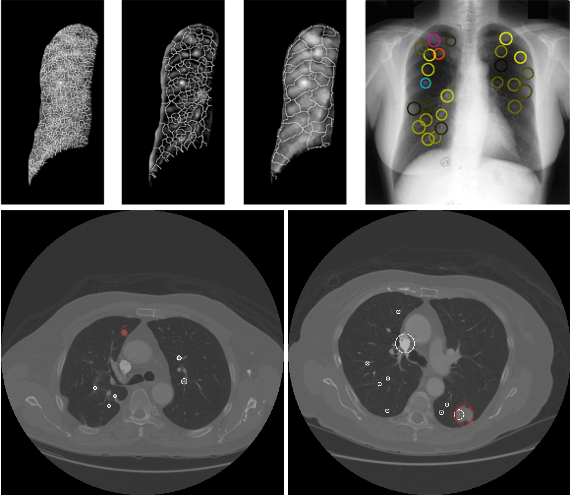

With the Lung CAD project we aim to create a computer-aided diagnosis system useful in the early detection of lung lesions, such as subtle lung nodules, or non-solid nodules such as ground glass opacities.

The purpose of the Biomedical Imaging Lab is to design and develop CAD systems that automatically detect and generate evidence to the radiologists that can optimise the early diagnosis and, therefore, maximise the medical treatments. Special focus is given to the early detection of subtle nodules and non-solid nodules such as ground glass opacities.